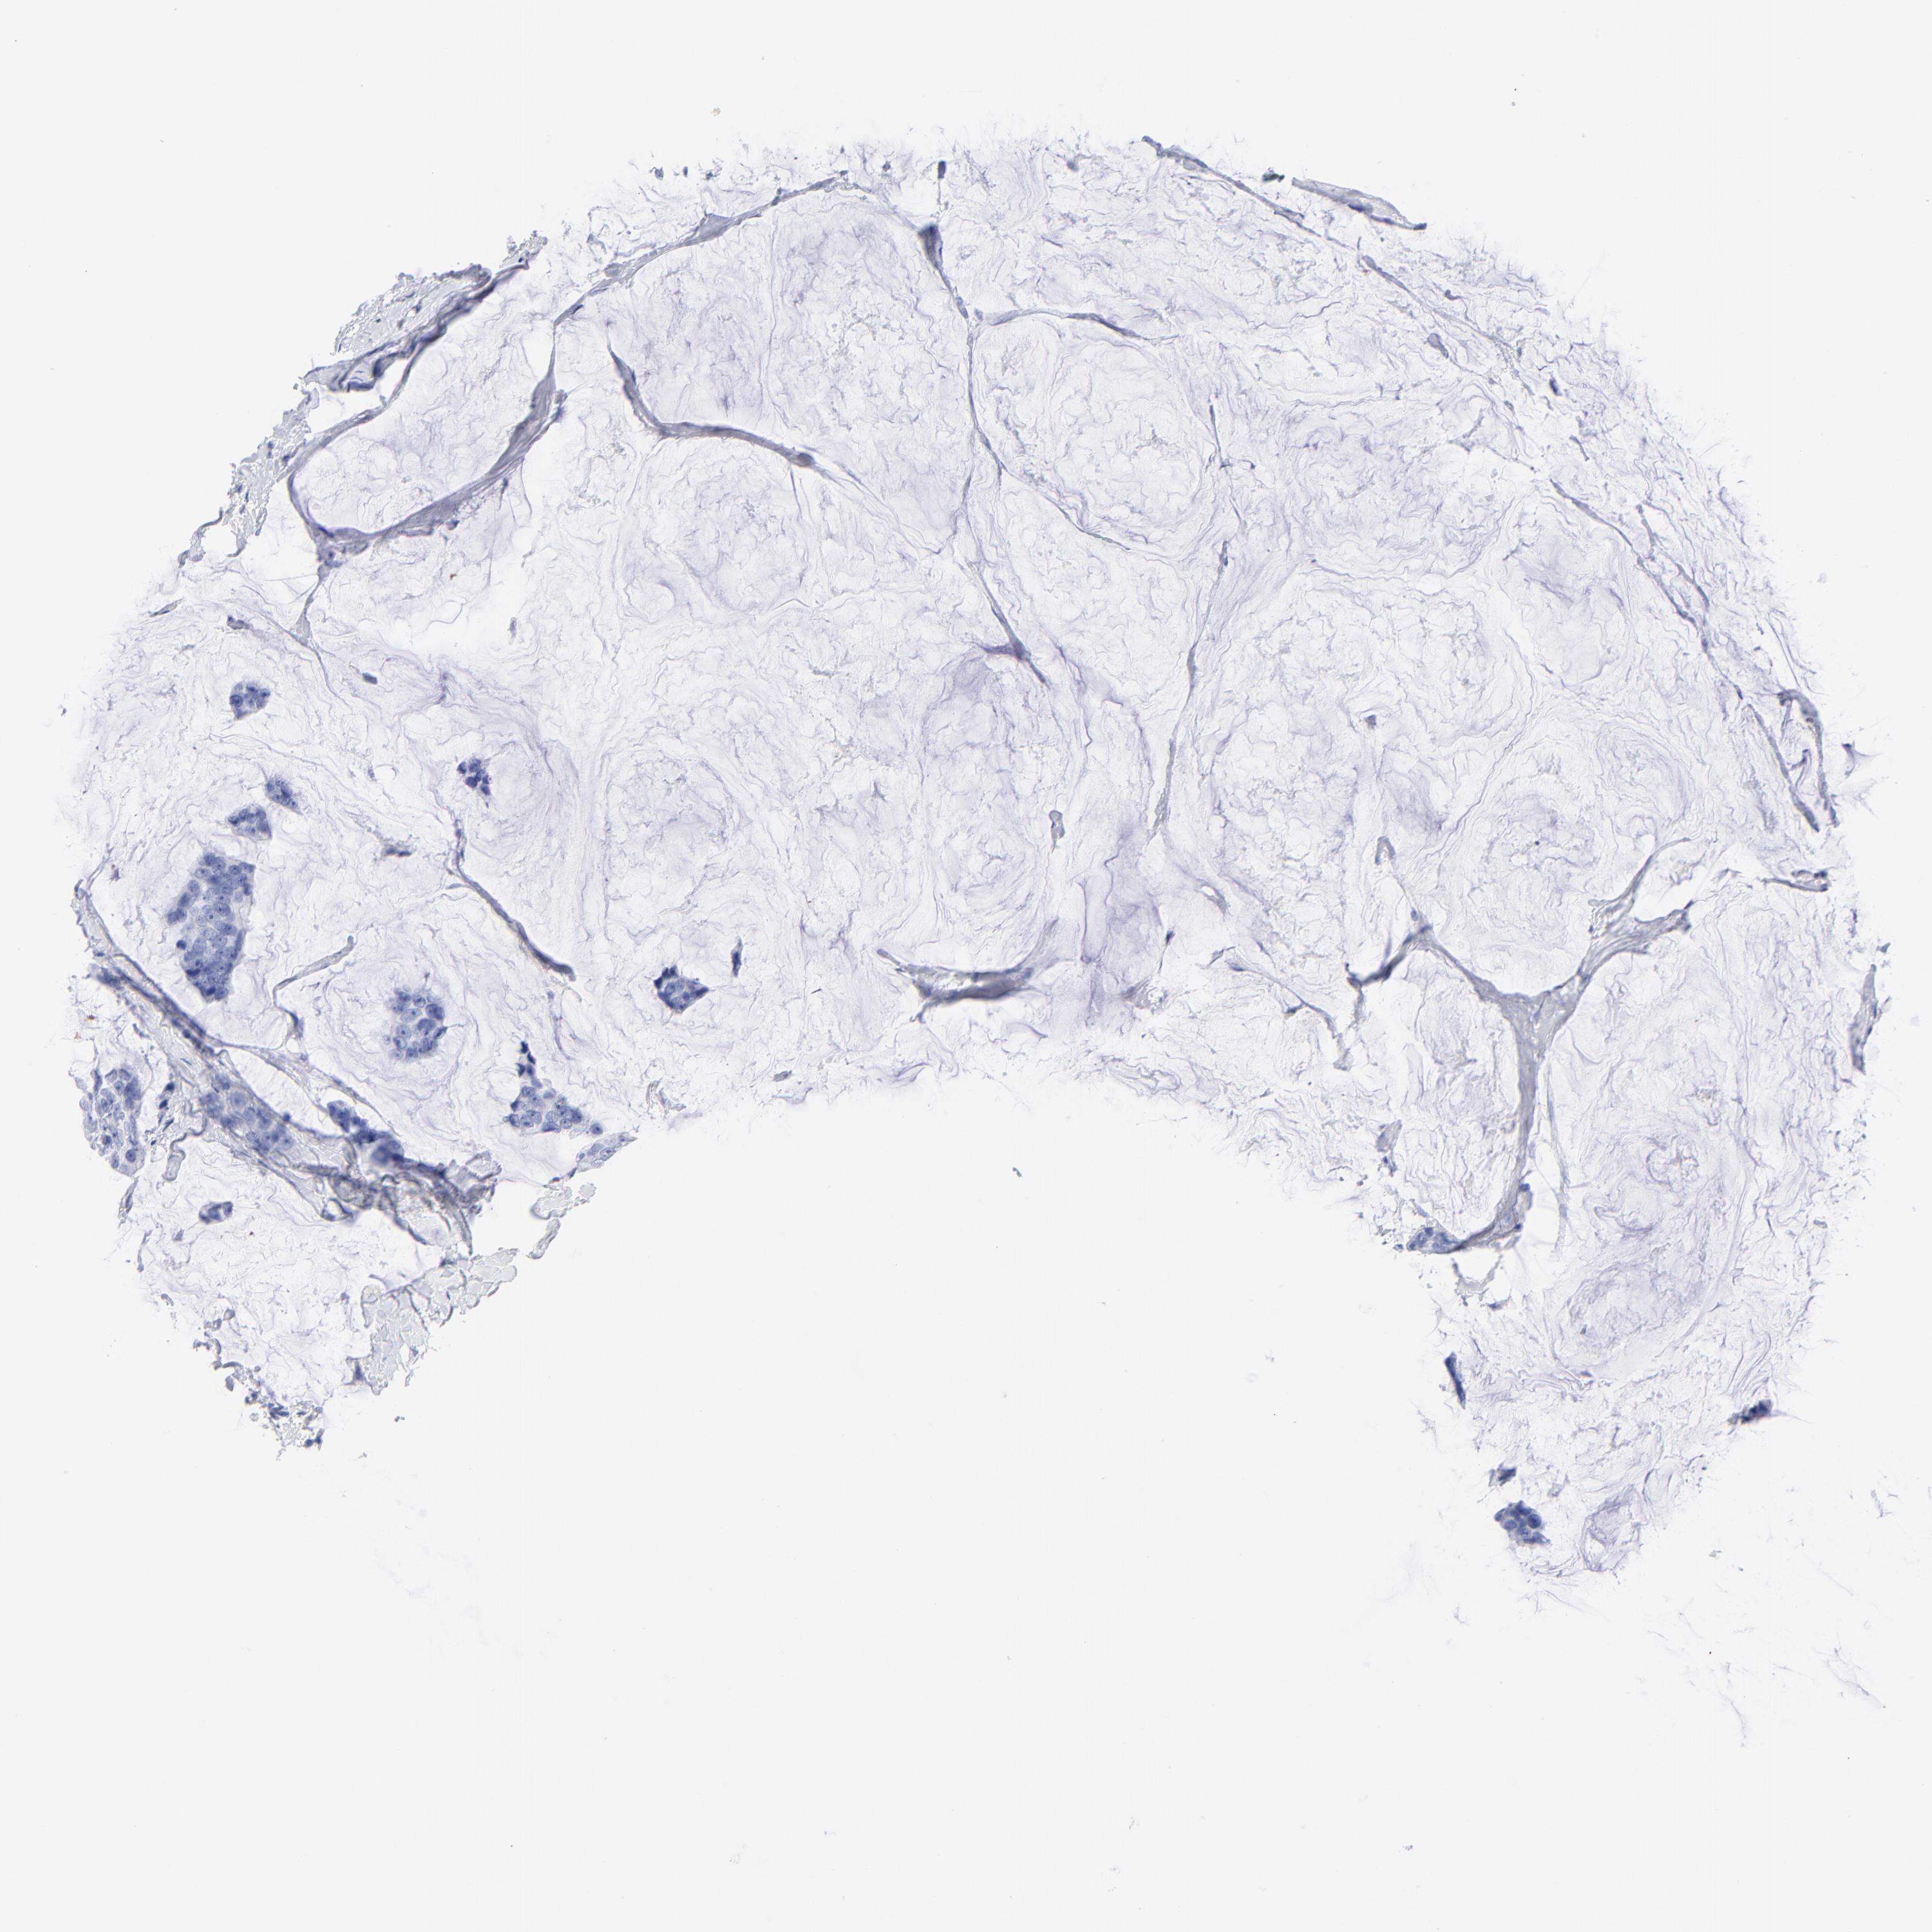

CANCER BREAST CANCER Show tissue menu

BRCA TCGA BRCA VALIDATION PROTEIN EXPRESSION